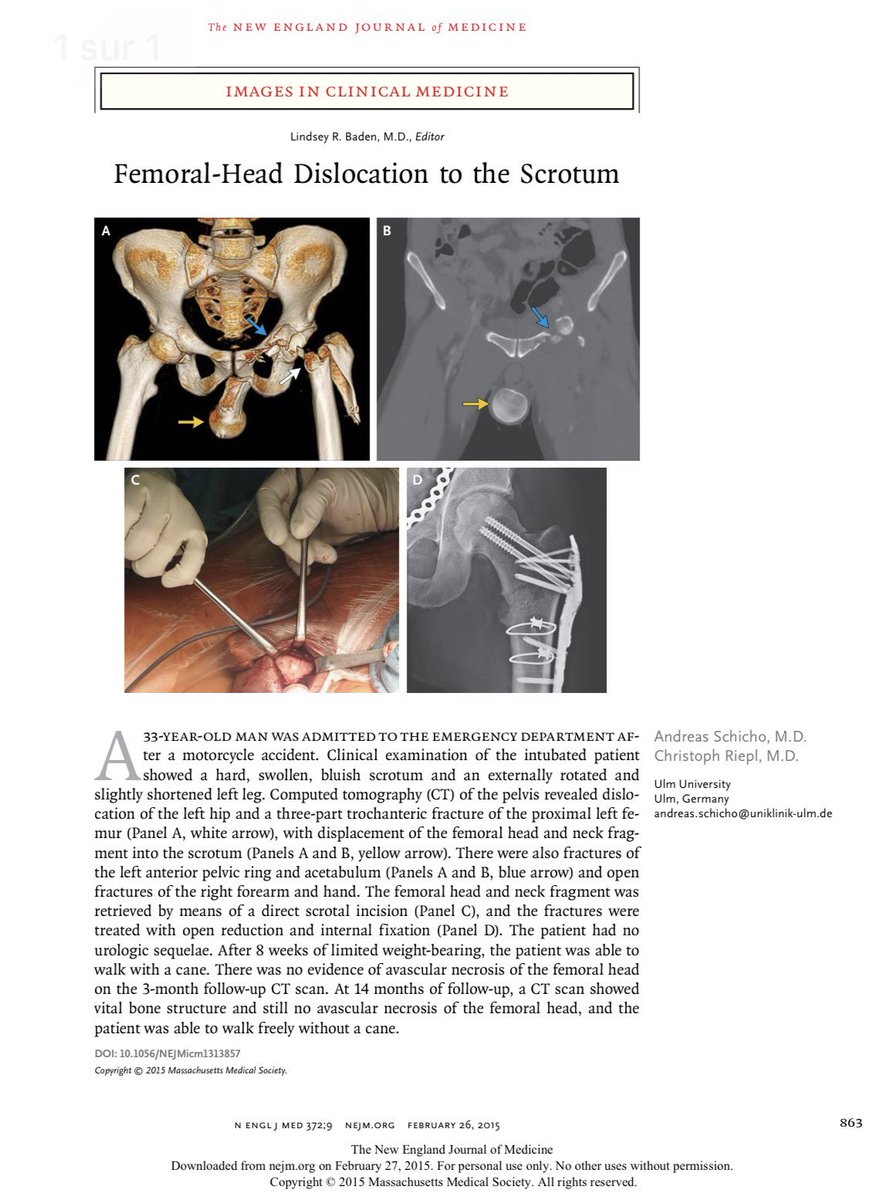

Exemple (il y en a des dizaines, avec cette radiographie)

"Une femme se fracture les hanches (bla bla) tableau de bord... (bla bla)"

"Horrifying X-ray shows why you should not put your feet on car dashboards"

"Bad car habit you need to stop"

Avec la caution Police, le message est encore plus fort ... "Police share shocking X-ray to show why you should not put your feet on car dashboards"

Vous remarquerez si vous cherchez que c& #39;est toujours la meme image, celle-ci  https://abs.twimg.com/emoji/v2/... draggable="false" alt="👇" title="Rückhand Zeigefinger nach unten" aria-label="Emoji: Rückhand Zeigefinger nach unten">

Et vous verrez que tous les articles indiquent que c& #39;est une femme, et jamais un homme, ce qui pourrait laisser penser que c& #39;est une habitude féminine... (il y a des stats ?  https://abs.twimg.com/emoji/v2/... draggable="false" alt="🤨" title="Gesicht mit hochgezogener Augenbraue" aria-label="Emoji: Gesicht mit hochgezogener Augenbraue">)

Or cette radio n& #39;est pas celle d& #39;une femme...

Or cette radio n& #39;est pas celle d& #39;une femme...

Mais celle d& #39;un enfant... comme on peut le voir ici (fléchés) car les cartilages de croissance des fémurs ne sont pas soudés (le trait noir entre l& #39;epiphyse et la métaphyse) contrairement à une hanche adulte.

(Il y a d& #39;autres signes en faveur d& #39;un enfant)

(Il y a d& #39;autres signes en faveur d& #39;un enfant)

Voilà d& #39;ailleurs comment cet enfant a été traité... Broches, vis et plaques... un coup de visseuse et Hop !

Se pose aussi la question de l& #39;origine de ces radiographies, qui n& #39;est pas claire... Il semble que coexistent deux origines :

- un accident de la route, mais la description d& #39;une femme rend celle ci assez peu crédible.

- une chute d& #39;une grande hauteur (un arbre).